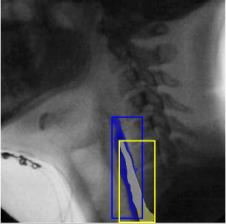

The videofluoroscopic swallowing study (VFSS) is a gold-standard imaging technique for assessing swallowing, but analysis and rating of VFSS recordings is time consuming and requires specialized training and expertise. Researchers have recently demonstrated that it is possible to automatically detect the pharyngeal phase of swallowing and to localize the bolus in VFSS recordings via computer vision, fostering the development of novel techniques for automatic VFSS analysis. However, training of algorithms to perform these tasks requires large amounts of annotated data that are seldom available. We demonstrate that the challenges of pharyngeal phase detection and bolus localization can be solved together using a single approach. We propose a deep-learning framework that jointly tackles pharyngeal phase detection and bolus localization in a weakly-supervised manner, requiring only the initial and final frames of the pharyngeal phase as ground truth annotations for the training. Our approach stems from the observation that bolus presence in the pharynx is the most prominent visual feature upon which to infer whether individual VFSS frames belong to the pharyngeal phase. We conducted extensive experiments with multiple convolutional neural networks (CNNs) on a dataset of 1245 bolus-level clips from 59 healthy subjects. We demonstrated that the pharyngeal phase can be detected with an F1-score higher than 0.9. Moreover, by processing the class activation maps of the CNNs, we were able to localize the bolus with promising results, obtaining correlations with ground truth trajectories higher than 0.9, without any manual annotations of bolus location used for training purposes. Once validated on a larger sample of participants with swallowing disorders, our framework will pave the way for the development of intelligent tools for VFSS analysis to support clinicians in swallowing assessment.